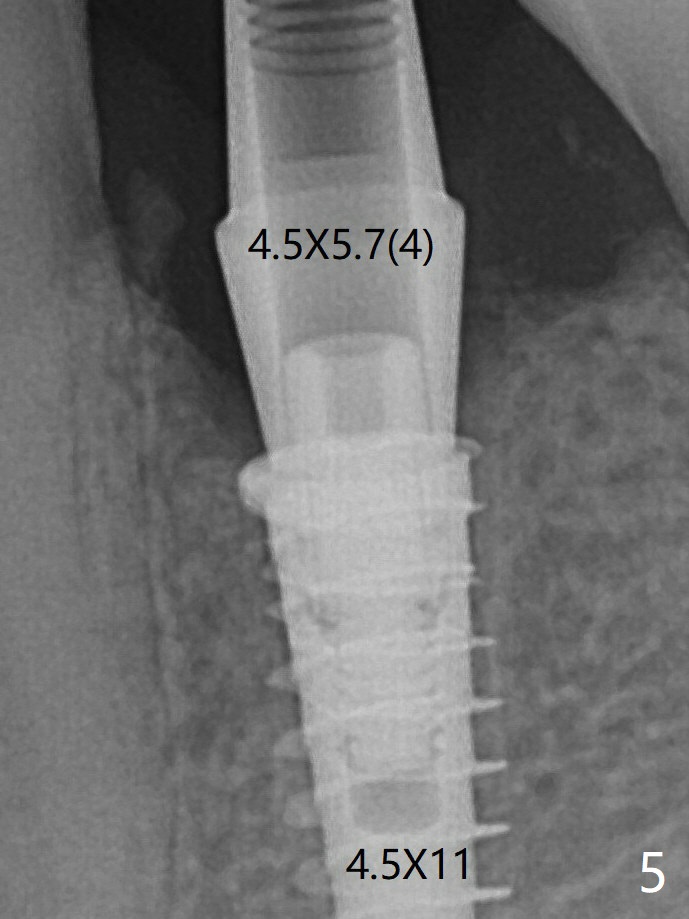

术后4个月骨粉好像不能形成牙槽嵴(图十二,与图五,六对比)。牙冠间隙可能无关大局(<)。